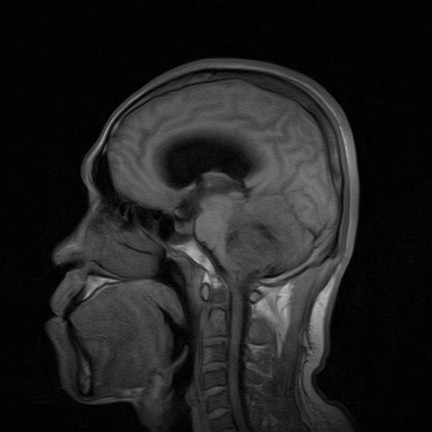

标题: MRI2064:少见病例。男性52,视力下降多年。 [打印本页]

标题: MRI2064:少见病例。男性52,视力下降多年。

四脑室区见混杂信号占位影,脑室系统扩张明显,临近结构显著受压称位,患者52岁,多考虑室管膜瘤可能性大

考虑第四脑室室管膜瘤并阻塞性脑积水。

考虑第四脑室室管膜瘤并梗阻性脑积水;部分性空蝶鞍;左侧上颌窦粘膜下囊肿。

考虑第四脑室室管膜瘤【血供丰富血管母细胞瘤可能】并梗阻性脑积水;部分性空蝶鞍;左侧上颌窦粘膜下囊肿。